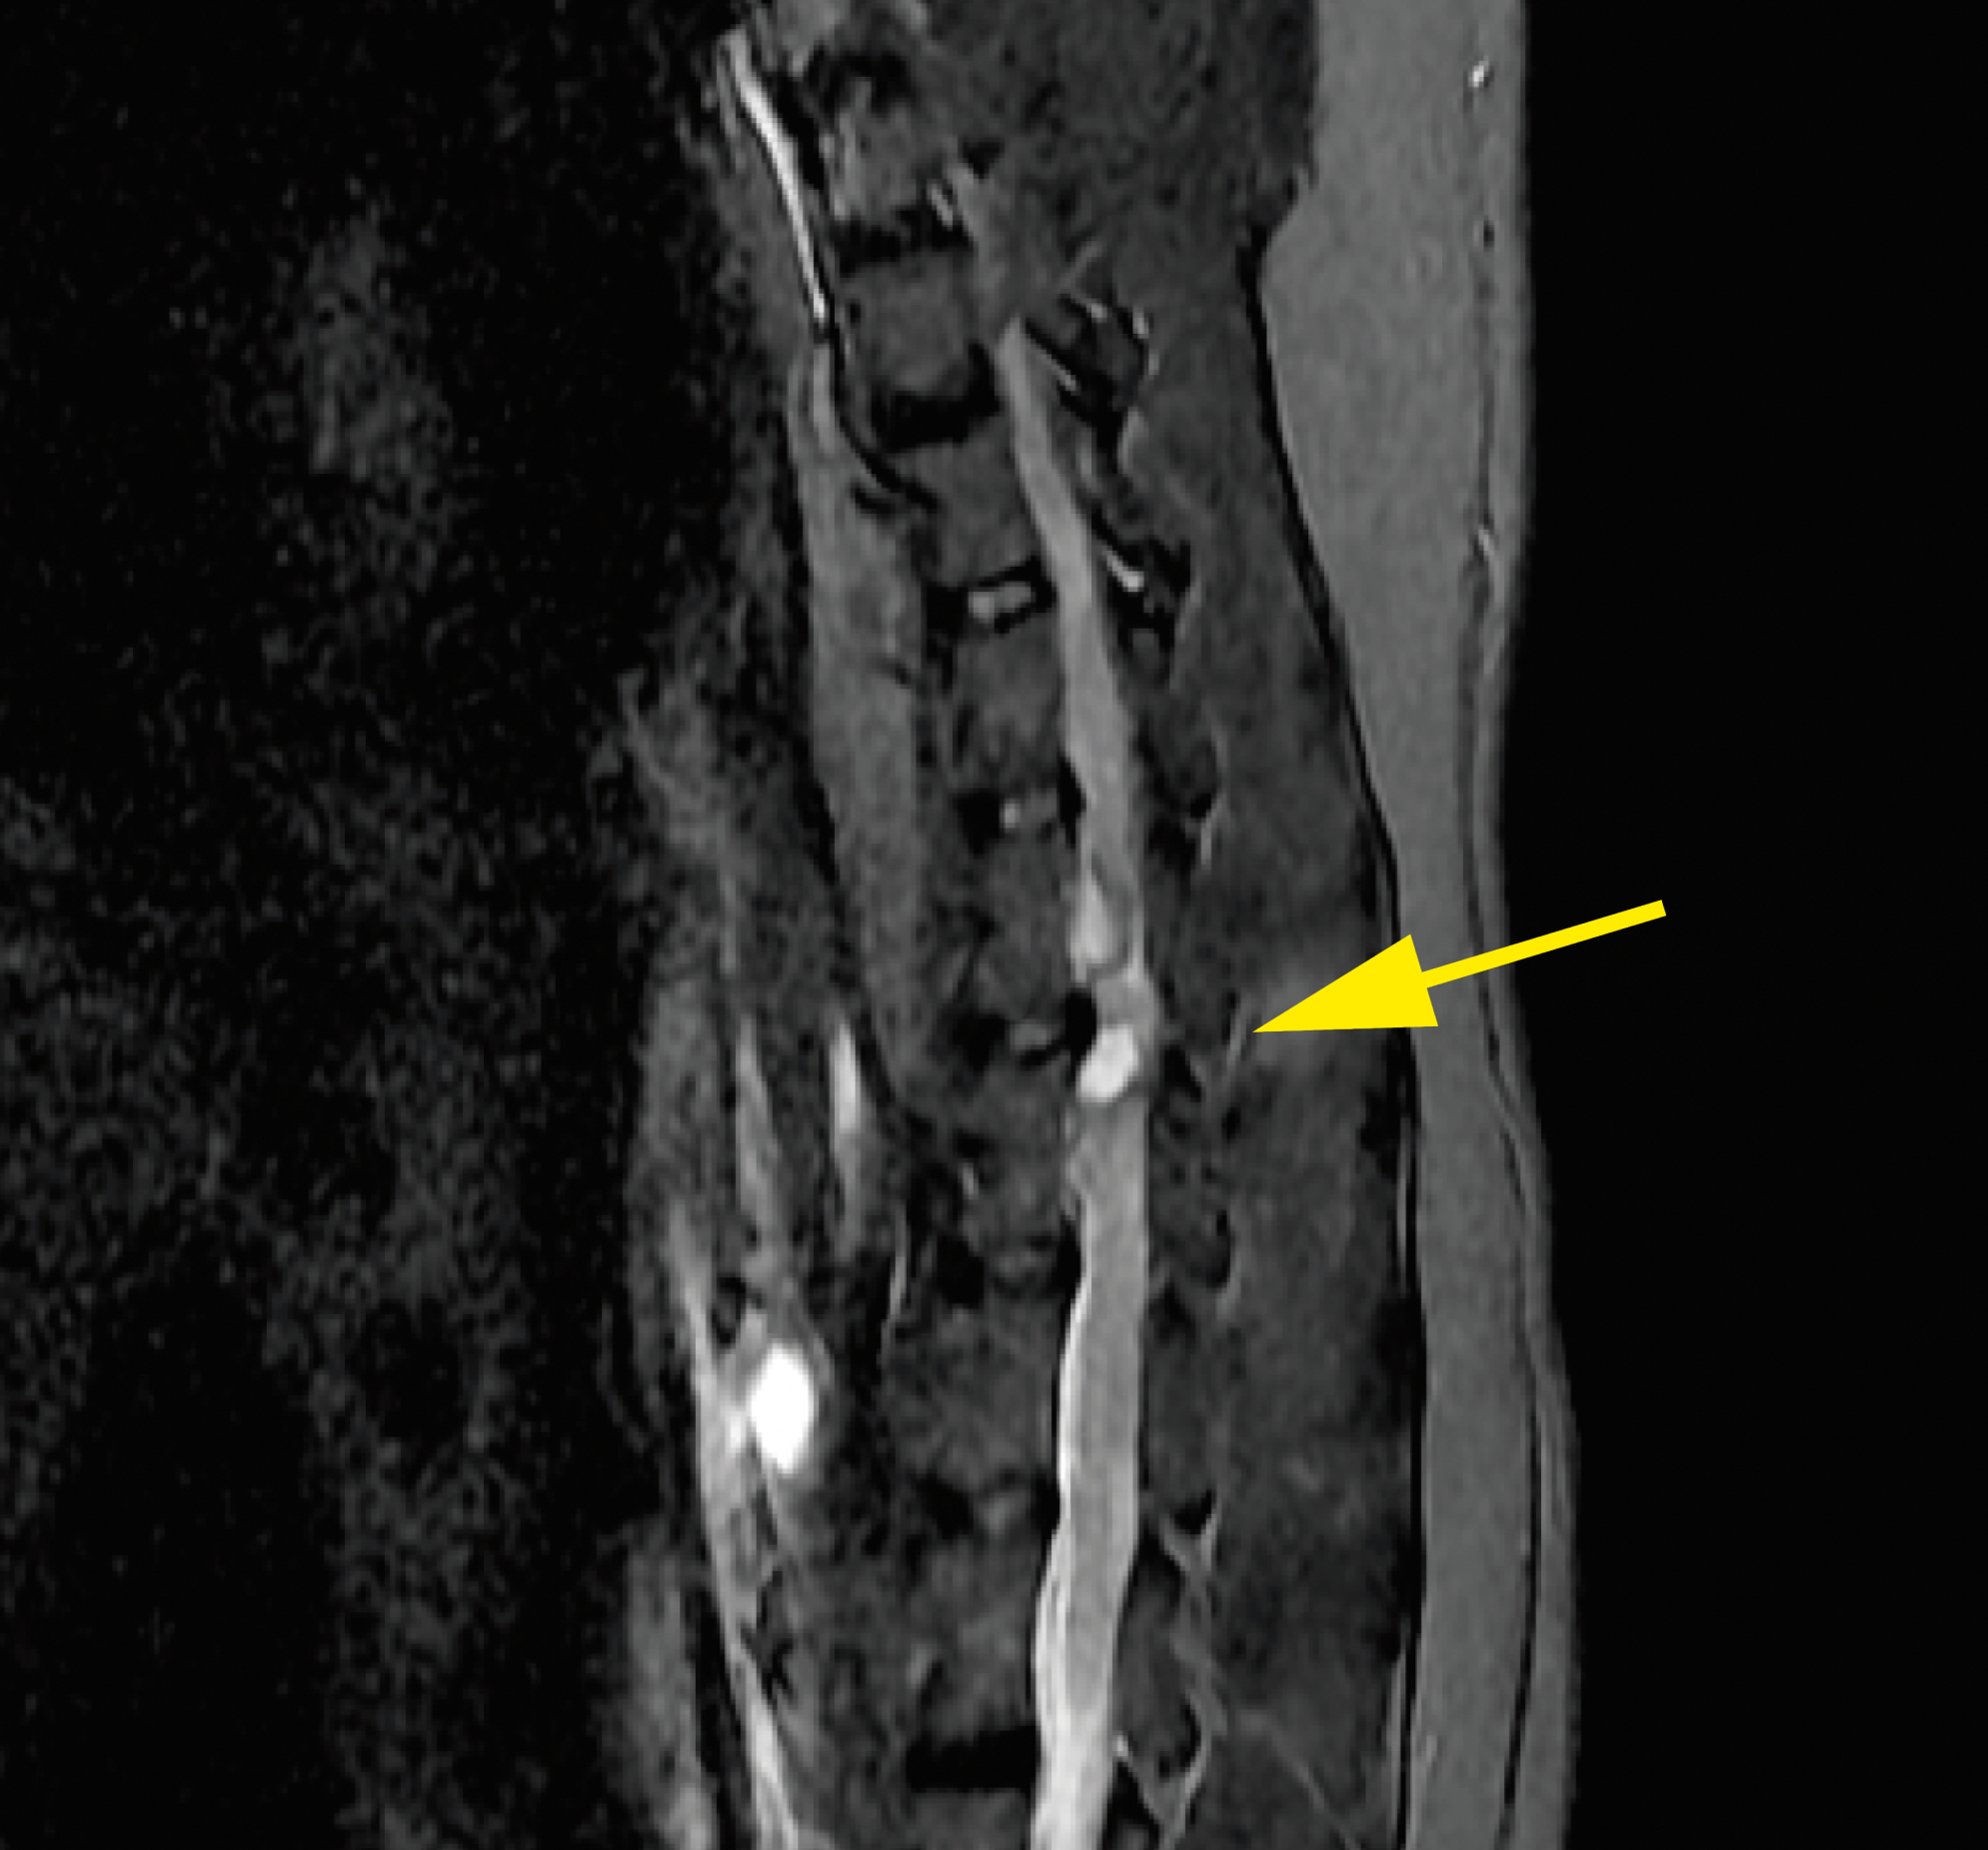

척수종양은 종양의 부위나 압박 정도에 따라 다양한 증상을 보일

수 있습니다.

보행 장애, 마비 증상, 통증이 일반적이며 종양의 종류 및 위치에

따라 권장되는

치료 방법이 달라집니다. Intradural extramedullary mass는

수술적 교정이 가능하며

일반적으로 수술한 이후 예후가 좋습니다. 환자의 상태에 따른

정확한 진단과 정교한 수술을

통해 환자의 회복을 위해

최선을 다하고 있습니다.